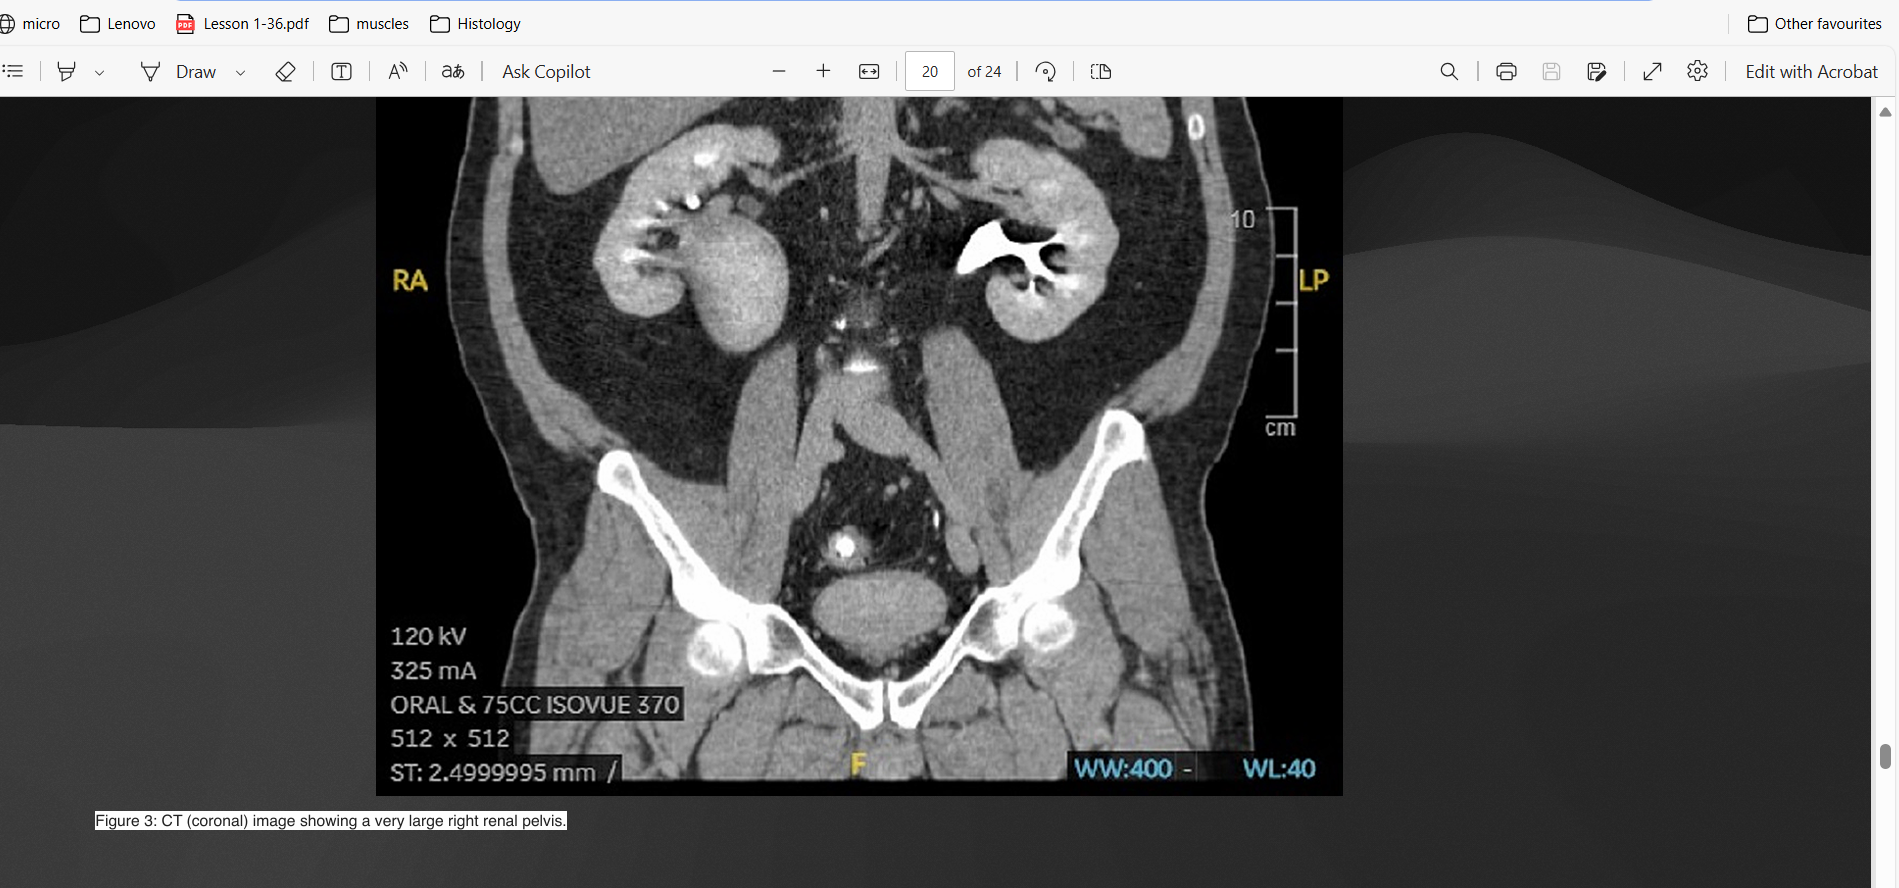

Screenshot 2025-02-15 215536.png

Screenshot 2025-02-15 215630.png